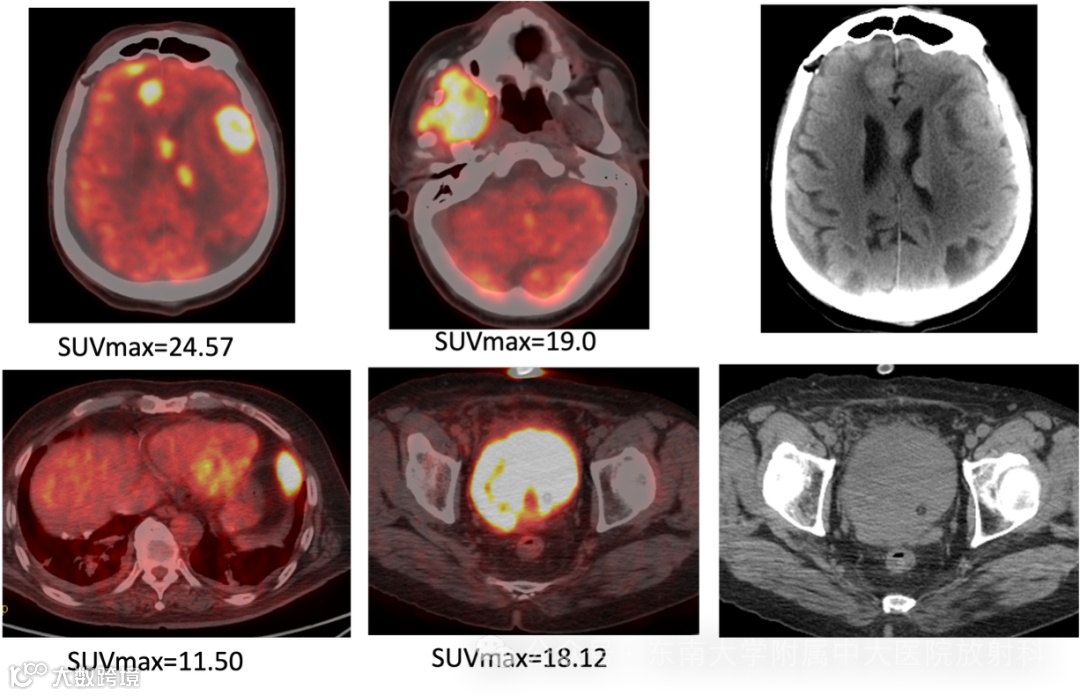

男,56岁

主诉:发现肉眼血尿3年余,加重1周

现病史:患者3年前无明显诱因下出现无痛性肉眼血尿,无血块,自然缓解,未予重视;1 周前加重,全程肉眼血尿;夜间小便 6-8 次,有尿频尿急,无尿痛,无排尿困难,无畏寒发热,无腰痛腹痛等;门诊拟以“前列腺增生”收住入院

实验室检查: LDH:432U/L ↑ (参考值100-240U/L)

fPSA:1.48ng/mL ↑ (参考值0-1ng/mL)

tPSA: 8.32ng/mL ↑ (参考值0-4ng/mL)